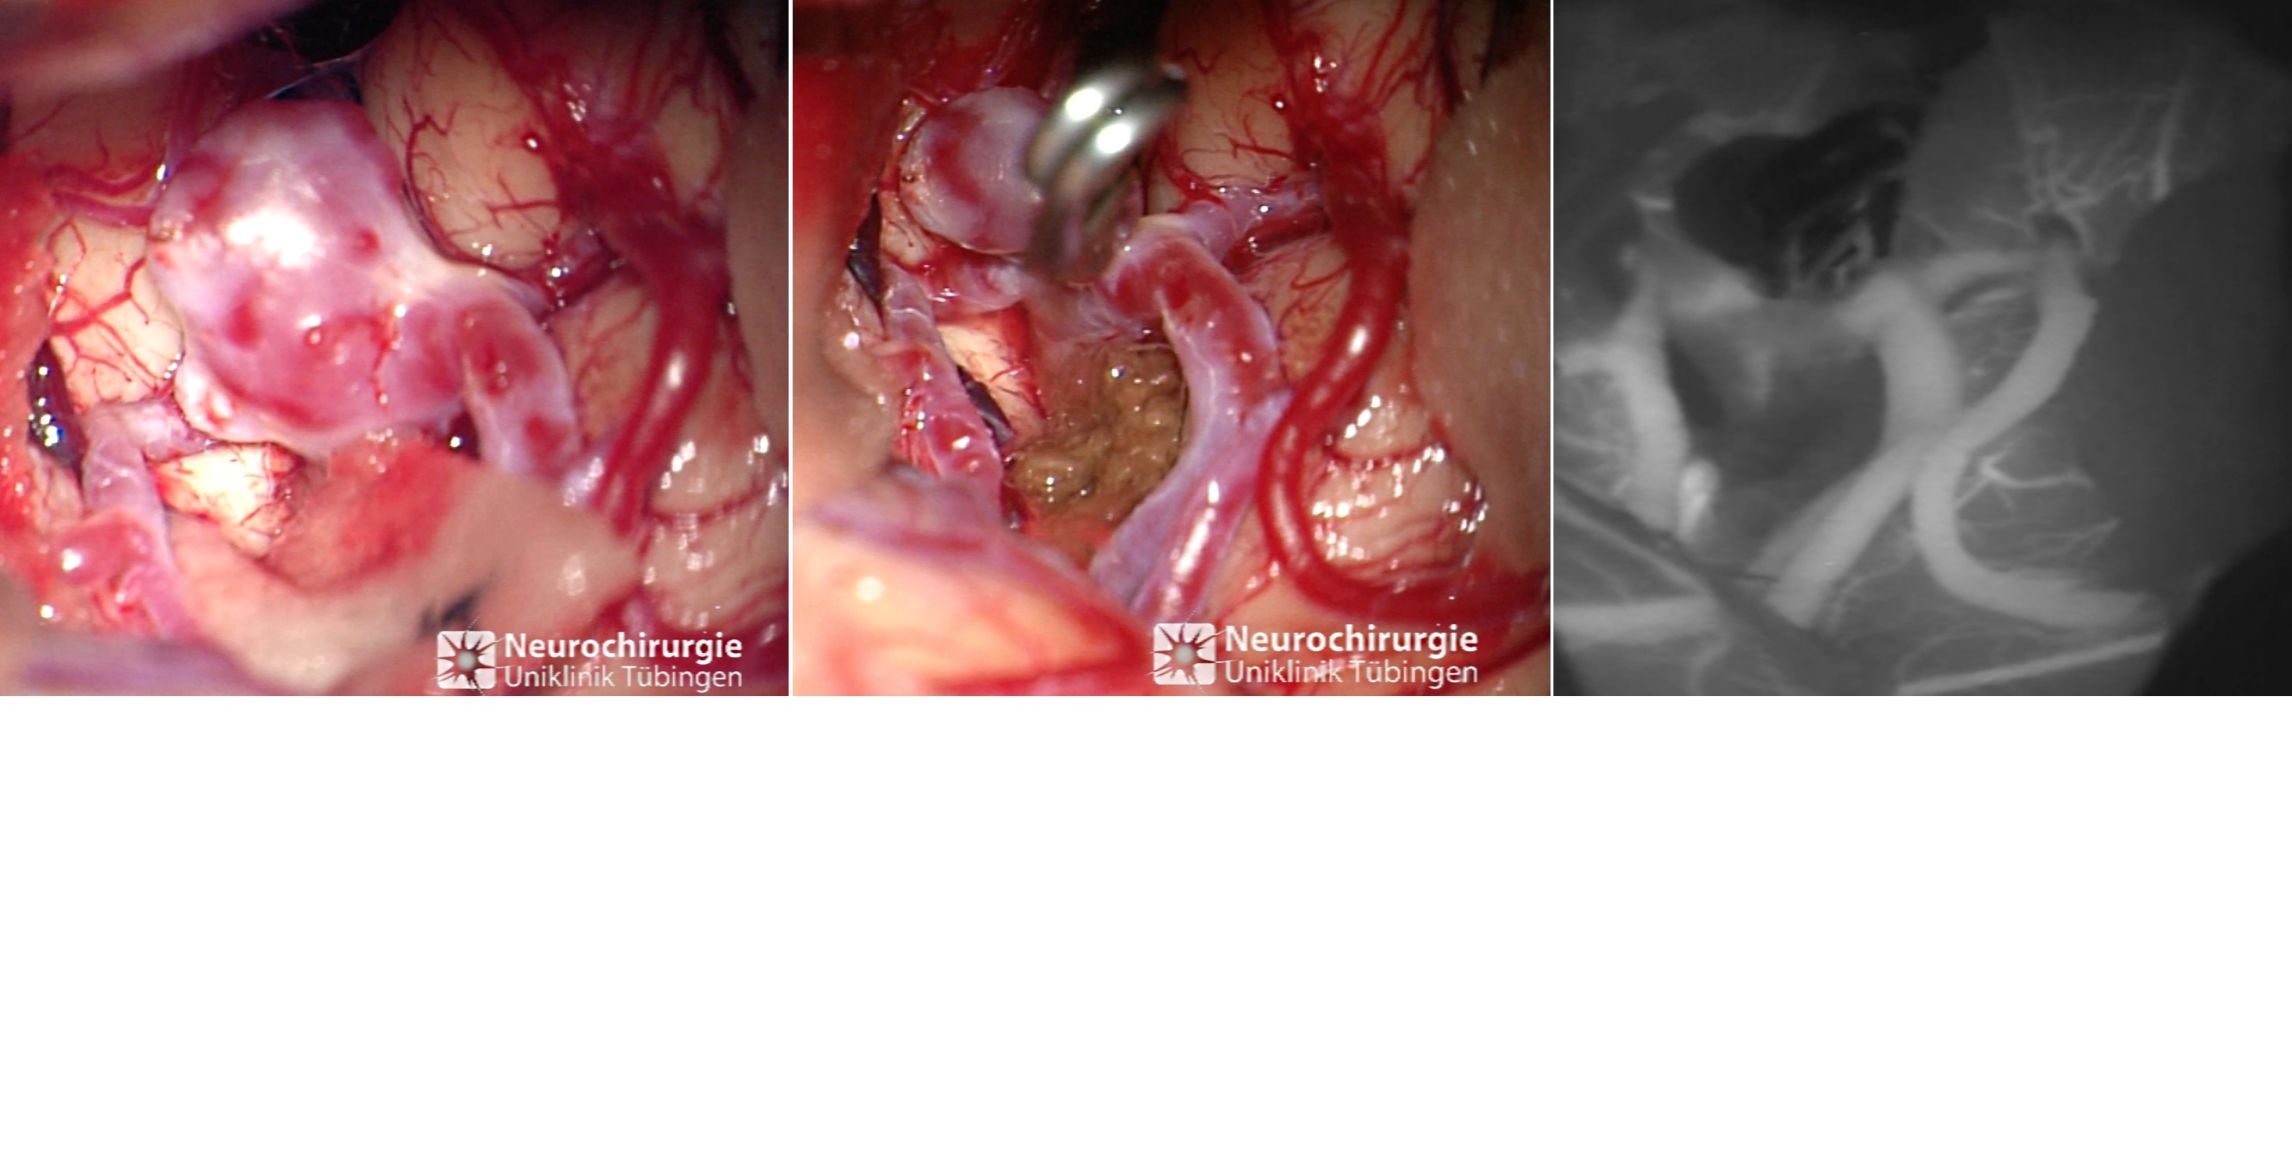

Die chirurgische Behandlung besteht in der Ausklippung des Aneurysmas. Dabei wird in mikrochirurgischer Technik ein kleiner Metallklipp aus Titan auf den Hals des Aneurysmas gesetzt und das Aneurysma so verschlossen. Eine erneute Blutung aus diesem Aneurysma ist damit nicht mehr möglich. Es gibt eine ganze Reihe unterschiedlicher Clips, die je nach Aneurysmaform und Lokalisation angewendet werden. Eine Clippingoperation wird minimalinvasiv unter dem Mikroskop durchführt, diese Operation dauert ca. 2-3 Stunden, je nach Größe und Lokalisation des Aneurysmas.

Intraoperatives Bild eines Aneurysmas

Intraoperatives Bild eines Aneurysmas vor (links) und nach (Mitte) dem Clipping. Rechts sieht man in der ICG Angiographie die vollständige Ausschaltung des Aneurysmas.